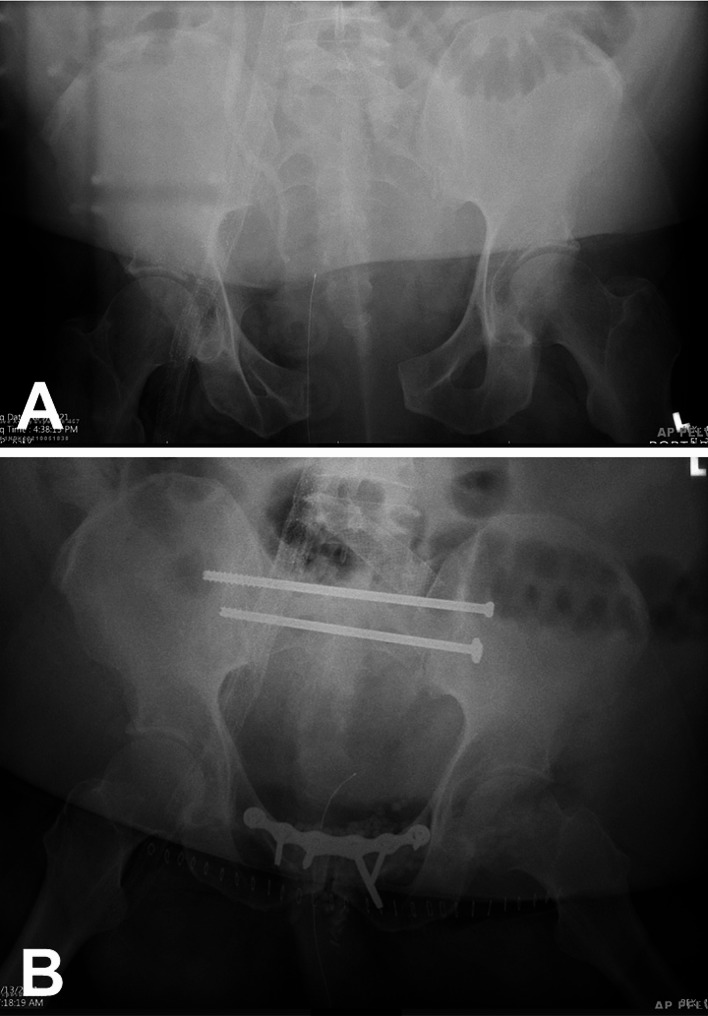

创伤性骨盆环损伤仍然是一项重大挑战,因为在同行评审的文献中,伤后死亡率高达 30%-40% 左右。潜在的可预防死亡率的主要根源在于对腹膜后出血程度和伤后凝血病的识别不及时。对骨盆创伤潜在病理生理学的了解是以损伤机制分级和损伤后凝血病风险分层的分类系统为基础的,而损伤机制分级和损伤后凝血病风险分层又会导致无法控制的失血性出血。这篇综述文章阐述了目前对严重骨盆创伤病理生理学的理解,重点是腹膜后出血的基本机制和相关不良后果。

Traumatic pelvic ring injuries continue to represent a major challenge due to the high rates of post-injury mortality of around 30-40% in the peer-reviewed literature. The main root cause of potentially preventable mortality relates to the delayed recognition of the extent of retroperitoneal hemorrhage and post-injury coagulopathy. The understanding of the underlying pathophysiology of pelvic trauma is predicated by classification systems for grading of injury mechanism and risk stratification for developing post-injury coagulopathy with subsequent uncontrolled exsanguinating hemorrhage. This review article elaborates on the current understanding of the pathophysiology of severe pelvic trauma with a focus on the underlying mechanisms of retroperitoneal bleeding and associated adverse outcomes.